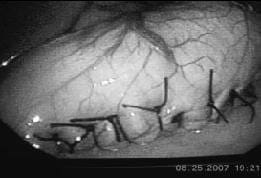

Se coloca la sonda contra la curvatura menor y se avanza hasta la región prepilórica. Se colocan puntos en seda cero separados entre la pared posterior gástrica y la anterior, y se crea así una plicatura gástrica desde el fondo gástrico, introduciendo el tejido gástrico hacia su propia luz. En su inicio en el ángulo de Hiss, la sutura debe quedar ajustada totalmente a la sonda oro-gástrica; hay que recordar que, al no haber resección de tejido gástrico y éste estar en su propia luz (imbricado), existe una mayor restricción de la que suponemos al mirar el remanente gástrico en su porción exterior, fácilmente valorable al movilizar la sonda y palpar con las pinzas laparoscópicas. Los puntos se extienden hasta los 3 cm del píloro y así creamos una restricción amplia (figuras 1-3).

FIGURA 3. Surset gástrico de Sales, plicatura completa.